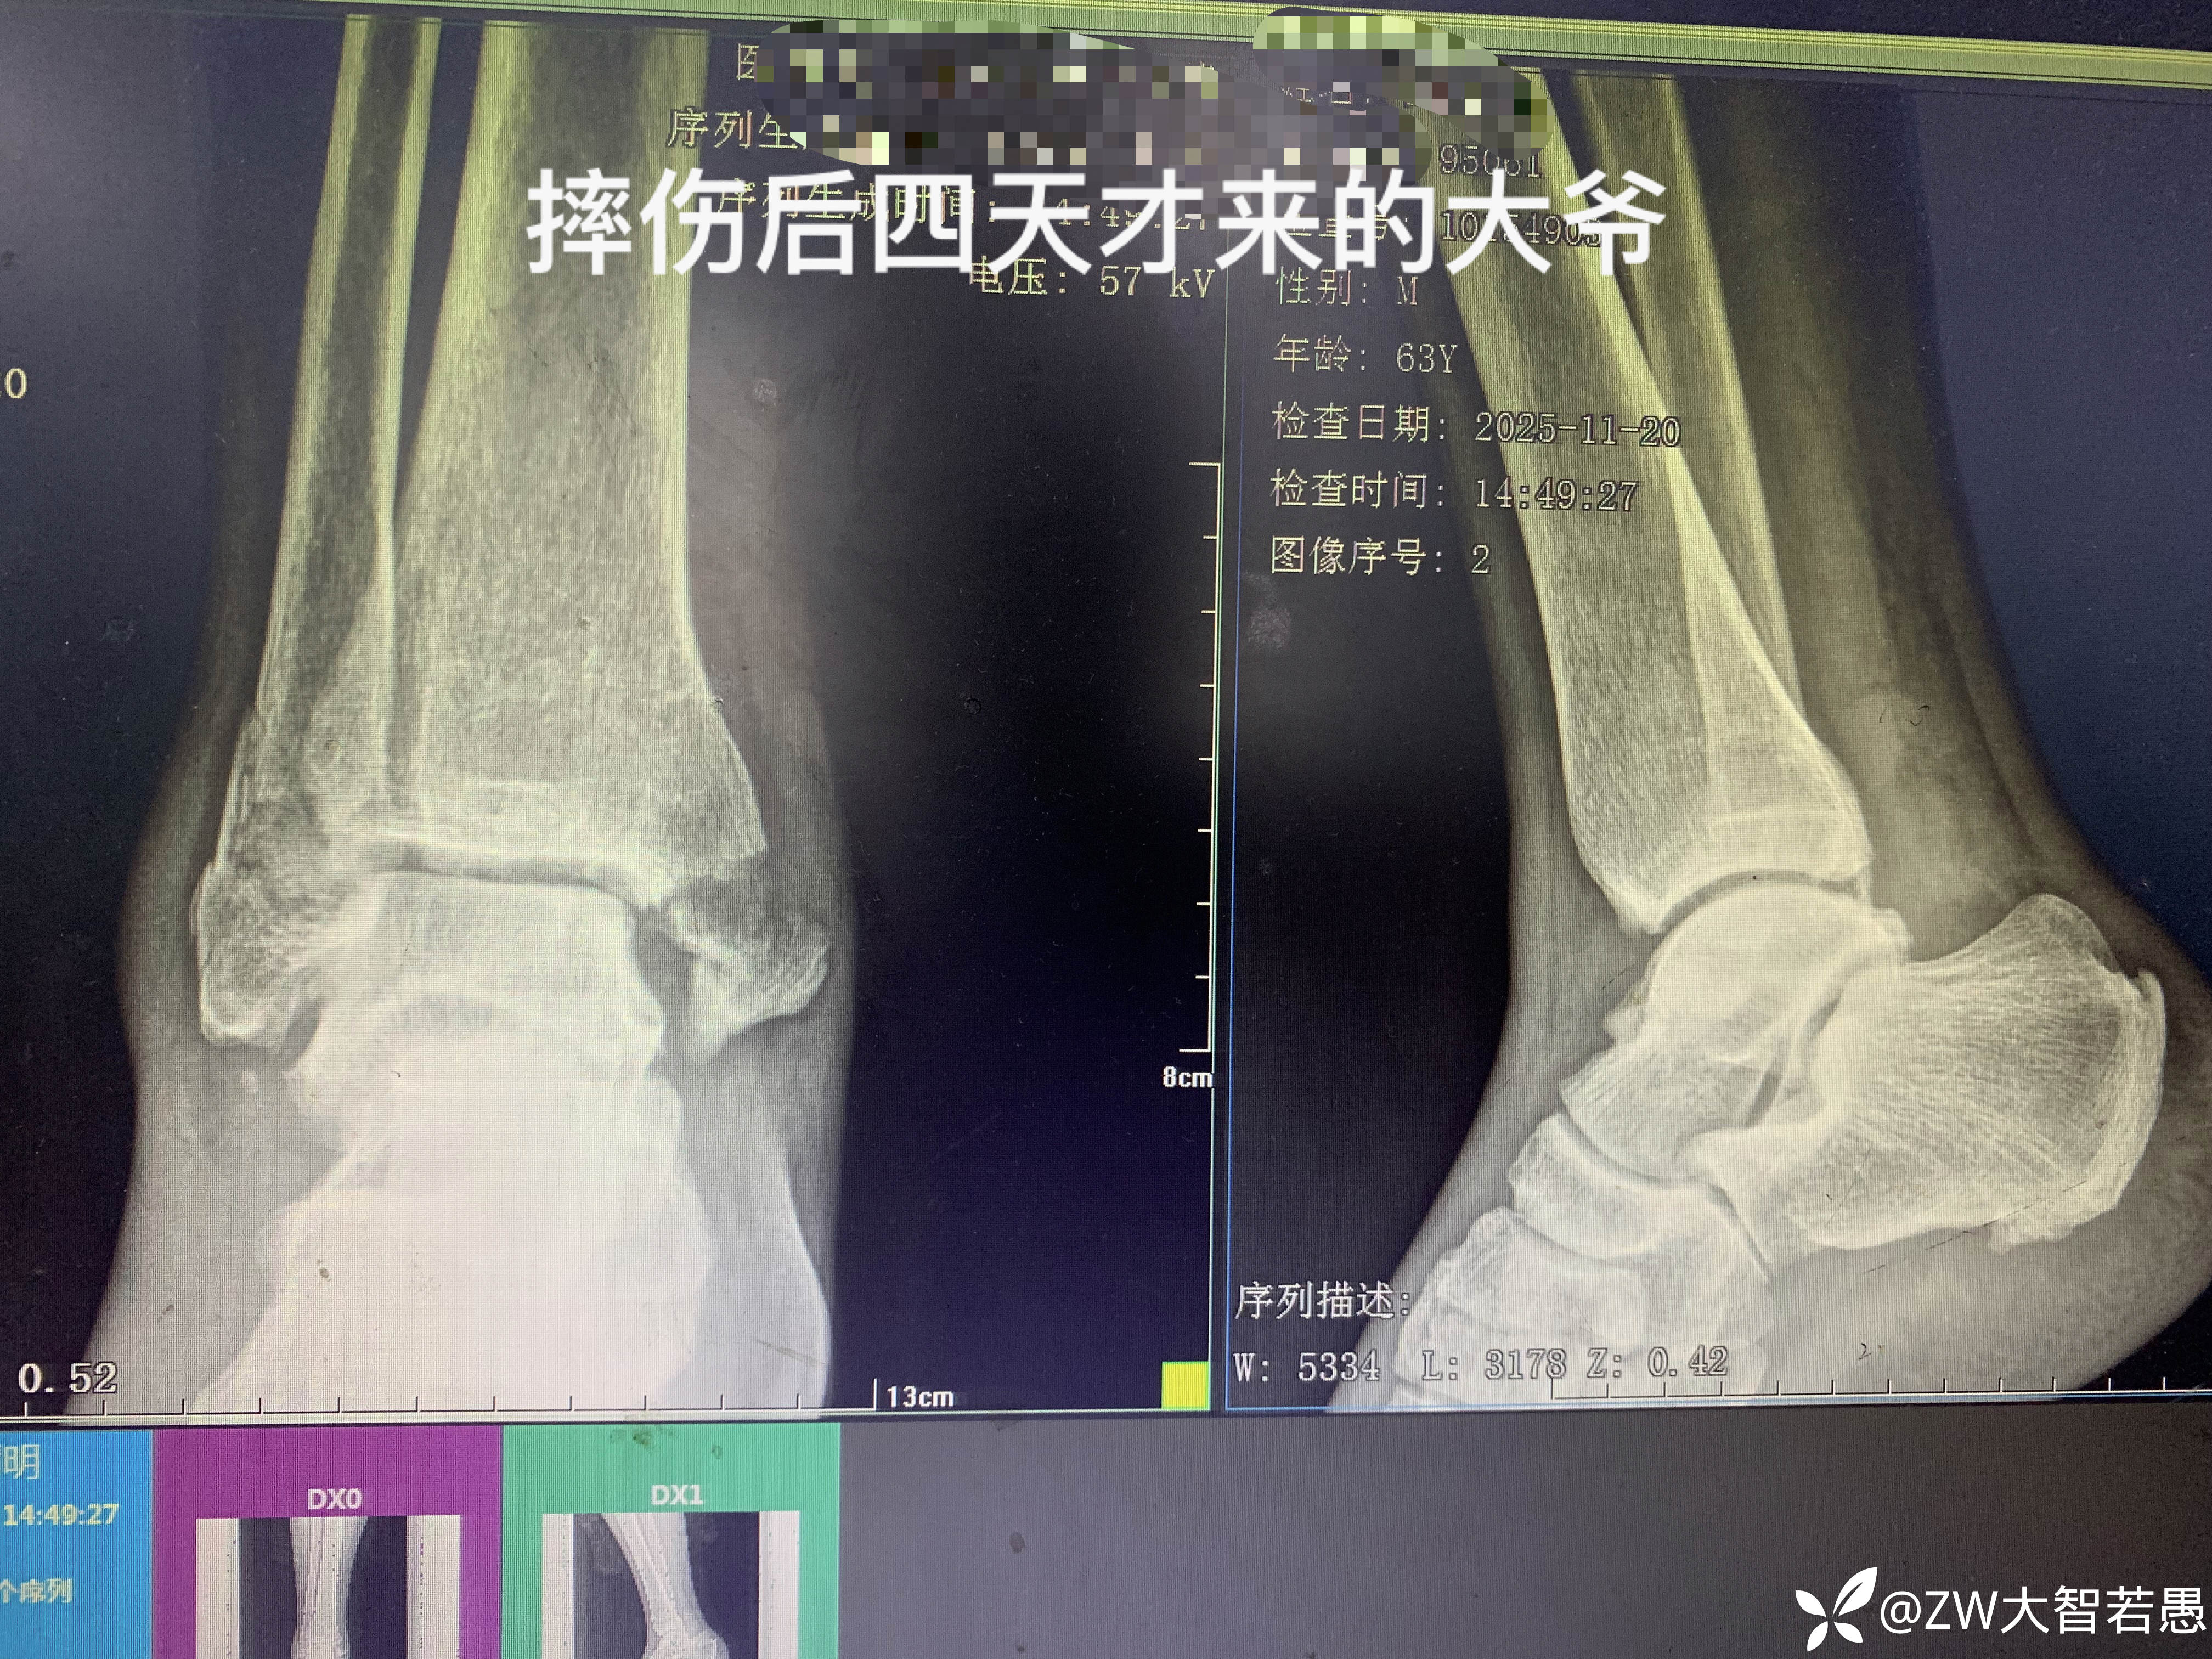

跟患者说要做手术,患者说做什么手术,我不做,、“走,去浏阳”

基层骨科医院的无奈……

病例不多,患者不相信……

破局方法……躺平,还是换个赛道?